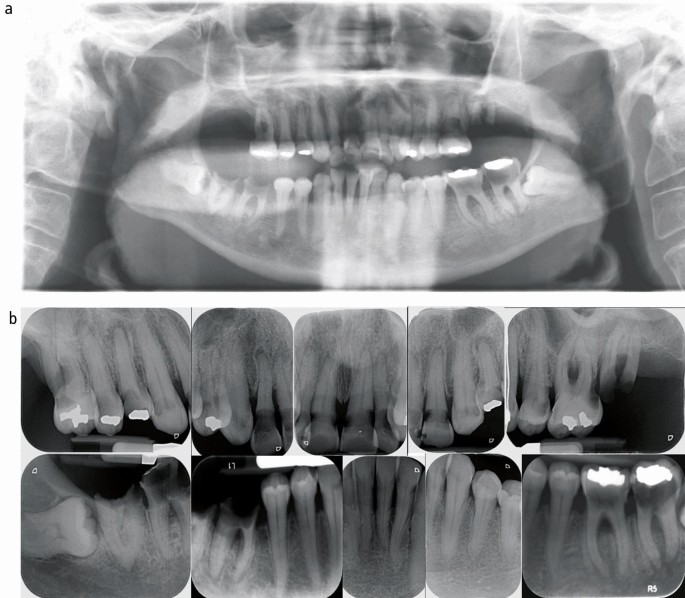

Extraoral examination revealed cutaneous pallor, multiple tattoos, finger clubbing, and weight loss (BMI = 16.1). Intraoral examination revealed mucosal pallor, moderate mouth dryness according to the Challacombe scale,17 chronic plaque-induced gingivitis, extensive cervical caries involving most teeth, and badly broken unrestorable lower right first and second molars, upper second molar, and upper first premolar (Fig. 1). Radiographic examination, including orthopantomogram (OPG) and full mouth periapical radiographs, revealed extensive cervical caries, impacted lower third molars on both sides, generalised horizontal alveolar bone loss consistent with chronic periodontitis, and furcational involvement of upper and lower molars (Fig. 2). The upper left and right lateral incisors were judged to be non-vital and unrestorable.